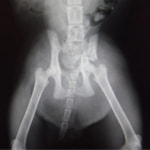

症例3:キルシュナーワイヤーのピンニングによる整復

ペルシャ猫 11ヶ月齢 雄

他院にて左大腿骨遠位の成長板骨折(salter-harrisⅠ型)が認められており、治療相談を目的として来院。当院にて、キルシュナーワイヤーを用いたピンニングにより骨折部位の整復を行いました。術後の経過は良好で、現在も経過観察中です。

術前レントゲン

術後レントゲン

機器

Arthrex社のターゲティングデバイスを用いてピンニングの位置を調整することで、確実な固定を行っています。当院ではこの手術器具以外にも、人の手術にも使用される様々な器具を導入し、手術精度を高め、また医療メーカーと新しい器具の開発、試作にも取り組んでおります。